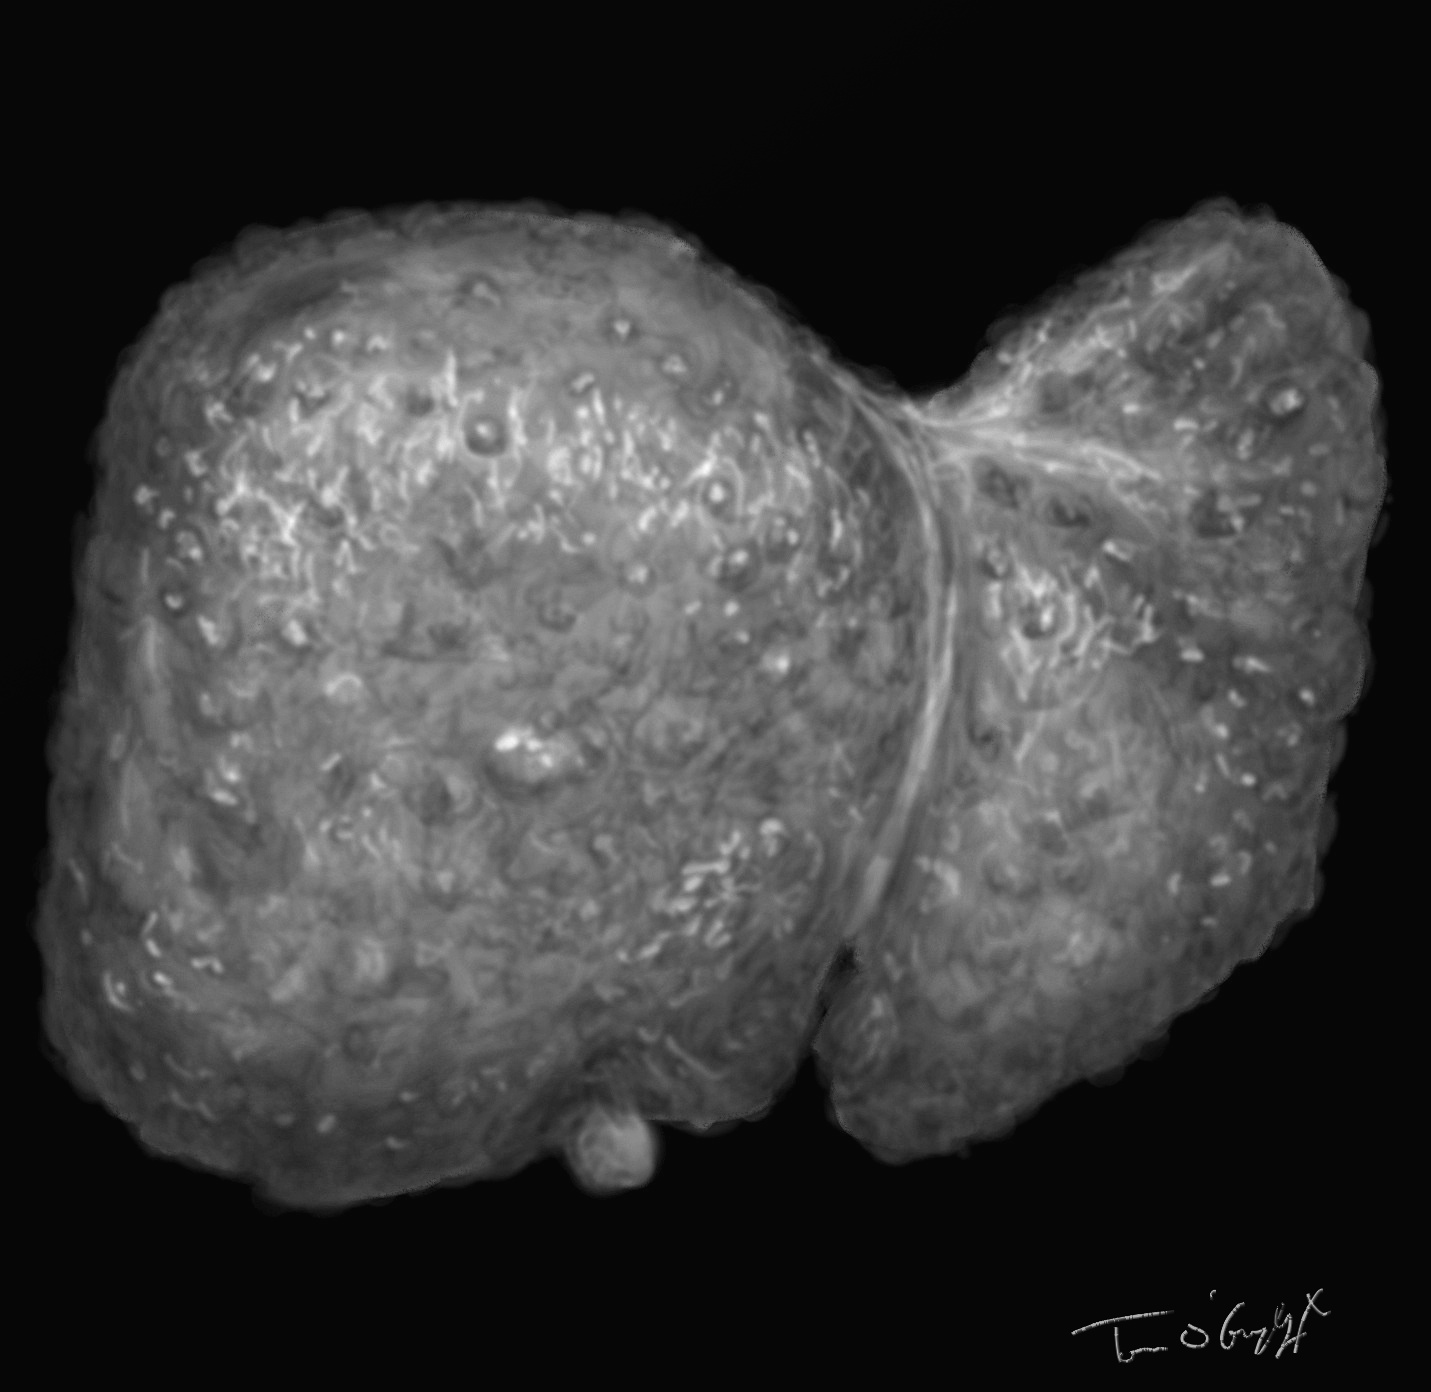

Le volume du foie est finalement variable au décours de la maladie, on peut percevoir une hépatomégalie à la palpation, dure, bosselée en cas de cirrhose macronodulaire. Mais elle devient difficile parfois dans les volumineuses ascites, et on peut aussi voir une atrophie du foie dans les évolutions terminales.

cirrhose hépatique secondaire à une hépatite C chronique, ascite très abondante et atrophie hépatique